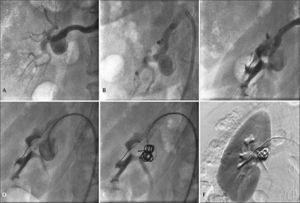

– Step-by-step remodeling technique for treatment of the type II renal artery aneurysm with 4F catheter. (A) Arteriography of the right renal artery. (B) Incidence used to visualize the distal main renal artery. (C) Balloon-expandable-stent implant in the aneurysm neck. (D) Catheterization of the aneurysmal sac with 4F JR catheter within the stent mesh. (E) Release of 0.035 coils in the aneurysmal sac. (F) Final renal arteriography.

The techniques used for the endovascular repair of RAA are described in Table 2. Four endovascular treatments were performed using the remodeling technique, employing 5 or 6mm×15 or 18mm Palmaz® Blue® balloon expandable stent, associated with 0.018’ AZUR® microcoils. The release of the coils was performed after catheterization of the aneurysmal sac with 4F diagnostic catheters or 2.4F Progreat® microcatheter, navigated by a 0.014×180cm guidewire (Figure 4). There were no renal artery dissections, perforations of the renal parenchyma, or arteriovenous fistulas in the periprocedural period.